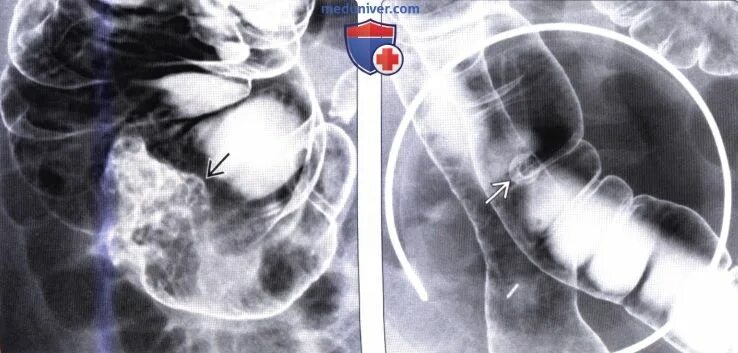

Полип ободочной кишки код по мкб 10